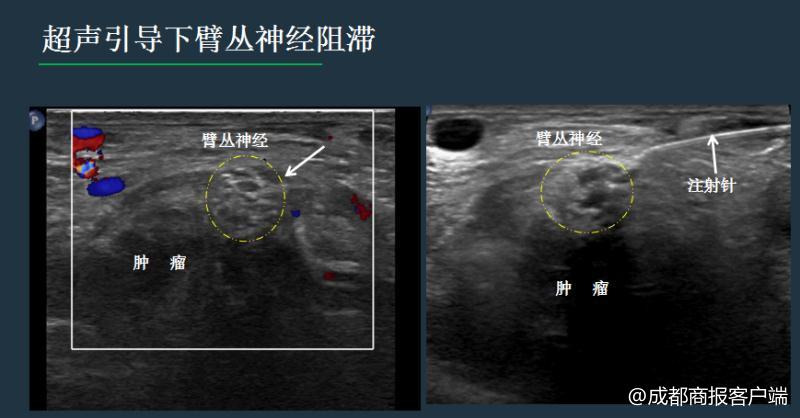

卢漫介绍说,神经的阻滞和毁损,既往多是凭体表解剖标记和医生的经验完成,由于神经的变异和不能看见穿刺针路径和针尖位置,易导致失败和意外。现在更多是在CT或超声引导下完成,但相比CT引导,超声无射线,通过屏幕上的实时显示,可以清晰看到穿刺针的路线,避开肠管、血管、骨头等,随时调整进针方向、深度,当针尖到达目标后,进行精准治疗。

同时,注射药物时,加上少量的超声造影剂,可以避免药物误入血管、直肠等重要组织,还可以实时评估药物的弥散范围,掌控用药分寸,预估效果。